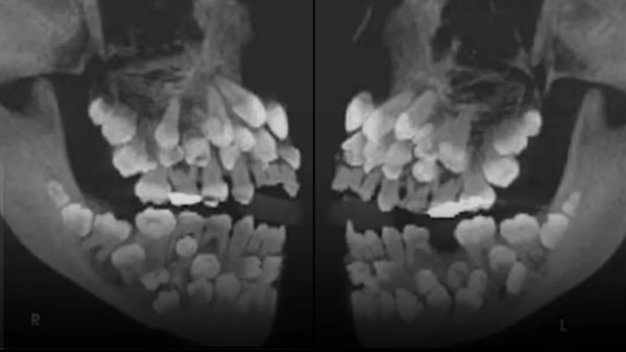

Vest o do sada nezabeleženom stomatološkom slučaju stiže nam iz Brazila. Lekari su otkrili jedanaestogodišnju devojčicu sa 81 zubom - najvećim brojem ikada dokumentovanim u ljudskim ustima. U pitanju je višestruka hiperdoncija, koja nastaje kada se dodatni (prekobrojni) zubi razviju preko onih uobičajenih. Većina ljudi sa hiperdoncijom ima jedan ili dva dodatna zuba - ali ovoliki broj je zaista neverovatan!

Ova mlada pacijentkinja nije pokazala znake nikakvog genetskog poremećaj, što slučaj čini potpunom medicinskom misterijom. Svaki dodatni zub varirao je u obliku i veličini, uzrokujući gužvu, deformaciju vilice i teškoće u normalnom žvakanju i govoru.

Rešavanje ovako složenog slučaja zahteva tim oralnih hirurga, ortodonta i protetičara, što često uključuje fazno vađenje zuba, praćenje rasta i rekonstruktivno planiranje tokom nekoliko godina.

Ovo retko stanje naglašava važnost rutinskih stomatoloških pregleda kod dece. Rani rendgenski snimci mogu otkriti skrivene dodatne zube pre nego što poremete normalno stanje u ustima. Roditelji treba da paze na odloženo nicanje zuba, neobičan razmak između zuba ili asimetriju lica - suptilne znake koji mogu ukazivati na ovu anomaliju.